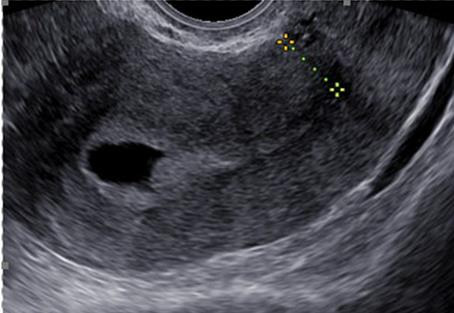

Background: A uterine niche after caesarean section may play a role in secondary infertility. The transvaginal approach is a newly developed minimally invasive surgical technique for repairing a uterine isthmocele.

Results: A total of 26 patients underwent a transvaginal uterine niche repair with an average operation time of 44 minutes. No major surgical complications were reported. 23 patients (88%) had good postoperative myometrial integrity, while 3 patients had a partial or complete postoperative recurrence of the uterine niche. The average pre- and postoperative myometrial thicknesses were 1.6 mm and 6.4 mm respectively. 64% of patients desiring pregnancy became pregnant after the transvaginal niche repair. There were no obstetric complications reported.

Conclusions: A transvaginal approach is a safe and effective technique for uterine niche repair. It offers good results in re-establishing myometrial integrity and may favour fertility outcomes. It represents a valid minimal invasive procedure for patients with a very thin residual myometrial thickness and secondary infertility without leaving a visual scar.